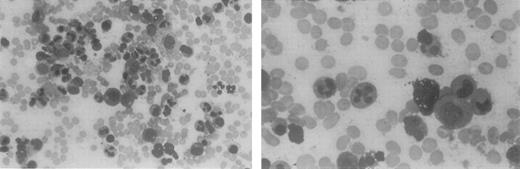

This 40-year-old woman was recognized as severely leukopenic and neutropenic when she was admitted to the hospital at age 5 with pneumonia. From early childhood through adulthood, numerous white blood cell counts of <1.0 × 109/L have been documented, with absolute neutrophil counts of 0.1 to 0.3 × 109/L and normal hemoglobin levels, hematocrits, and platelet counts. Her clinical history is remarkable for gingivitis and episodic cutaneous and sinopulmonary infections. Examination of bone marrow aspirates obtained from childhood through adulthood has revealed a hypercellular marrow with marked granulocytic hyperplasia. Bone marrow neutrophils in these aspirates contain hypersegmented nuclei with highly condensed chromatin. The nuclear lobes are often separated by long, thin strands of chromatin, consistent with the diagnosis of myelokathexis (Figure1). Many reticuloendothelial cells within the bone marrow contain basophilic material. Cytogenetic examination results on multiple occasions have been normal. At age 12, she had mild hypogammaglobulinemia (IgG, 525 mg/dL). The neutropenia was attributed to the ineffective production of neutrophils, based on a quantitative bone marrow biopsy and ferrokinetic studies performed in 1971.

Bone marrow aspirate from a patient with myelokathexis, revealing abundant cells of the neutrophil lineage.

Characteristic pyknotic nuclear lobes connected by fine chromatin filaments are present in the mature neutrophils.

Bone marrow aspirate from a patient with myelokathexis, revealing abundant cells of the neutrophil lineage.

Characteristic pyknotic nuclear lobes connected by fine chromatin filaments are present in the mature neutrophils.

Bone marrow aspirates were hypercellular, and neutrophils were hypersegmented with nuclear lobes connected by thin filaments of chromatin (Figure 1). To determine the relative distribution of bone marrow myeloid compartments in patients with myelokathexis, we examined bone marrow CD34+ cells in colony-forming assays in soft agar in the presence of a cocktail of hematopoietic growth factors (SCF, Flt3 ligand, IL-3, G-CSF, and GM-CSF). On day 15, the resultant colonies were evaluated based on their morphology, density, and number of cells, and they were grouped into CFU-HPP (high proliferative potential primitive progenitor cells, more than 1000 cells/colony), early myeloid progenitors CFU-GM (more than 100 cells/colony), and late myeloid precursor CFU-GM clusters (<50 cells/colony). Colony-forming assays demonstrated that the proportion of CFU-HPP cells was increased, but the proportion of early and late CFU-GM cells was relatively decreased in patients with myelokathexis (Figure3). These data indicated a shift in the relative distribution of bone marrow myeloid compartments to more “primitive” cells in myelokathexis.